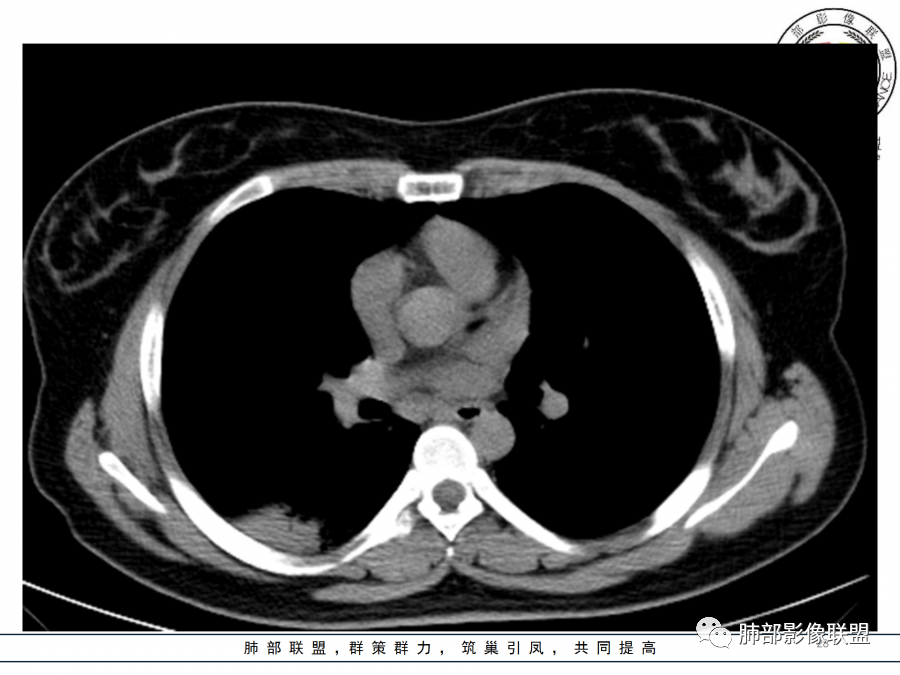

年轻女性,急性病史,发热,WBC17.42*10^9/L,NE%82.8%,

痰革兰染色示:G-杆菌1+、G+球菌1+,未检出真菌,抗酸染色阴性。

1.年轻女性,咳嗽、发热(38.8°),起病急,血象高。影像上大片实变影为主,一般会首先考虑细菌性肺炎,尤其是肺炎链球菌感染等。疗效不满意时考虑其他。

2.影像上怀疑其他病灶的理由有:

1)实变影为大小不等多中心性。

2)沿胸膜下分布趋势(不同于大叶性肺炎的肺叶“造型”)。

3)周围较大范围磨玻璃影及小叶间隔增厚。

4)病灶体积增大明显(叶间裂推移)。